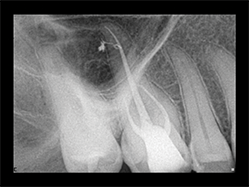

Slika 5:Prikazuje slučaj pogodan za reviziju punjenja s obzirom na loš rezulatat prethodne terapije kanala korena. Uz odgovarajuću obradu i irigaciju(Sleimanova faza) i zahvaljujući teškoj ali uspešnoj potrazi za distalnim kanalom, izvršena je 3-D opturacija kanala koja pokazuje suženje između mezijalnog i distalnog kanala kao i veoma visoko postavljene lateralne kanaliće u palatinalnom kanalu.